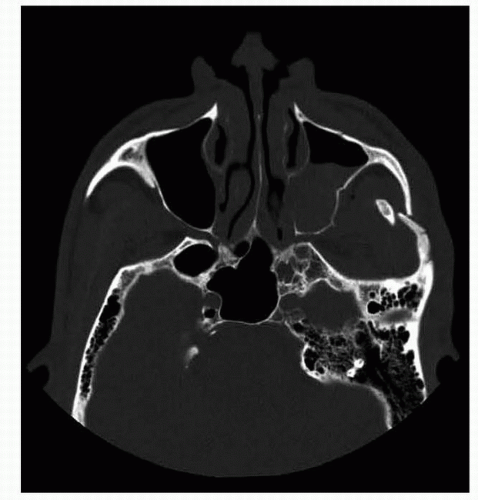

IMAGING

The appropriate radiologic workup requires fine-cut CT.

The ideal workup includes axial cuts, reformatted coronal cuts, and sagittal cuts through the orbit.

For our sagittal reformatting, we prefer oblique parasagittal cuts through the orbit that follow the axial line of the optic nerve.

In special cases of complex or comminuted fractures, a 3D reformatting may also be very useful.

FIG 1 • ZMC showing fracture of four processes of the zygoma— maxillary, frontal, orbital and temporal.

Zygomatic fractures are fractures of the zygomatic bone together with any one or all of its four processes—maxillary, frontal, orbital, and temporal (FIG 1).

More often, fractures involve the adjacent bones through the other processes, and the term zygomatic complex or zygomaticomaxillary complex (ZMC) fracture is more appropriate.